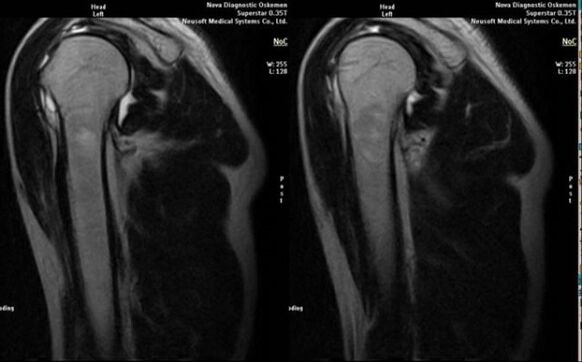

- magnetic resonance and computed tomography;

Signs that indicate the development of arthrosis directly include the appearance of a significant narrowing of the joint space, sclerosis of the subcartilaginous structures, thinning of the chondrocyte layer itself, the appearance of osteophytes and the deposition of salt crystals in the intra-articular fluid.